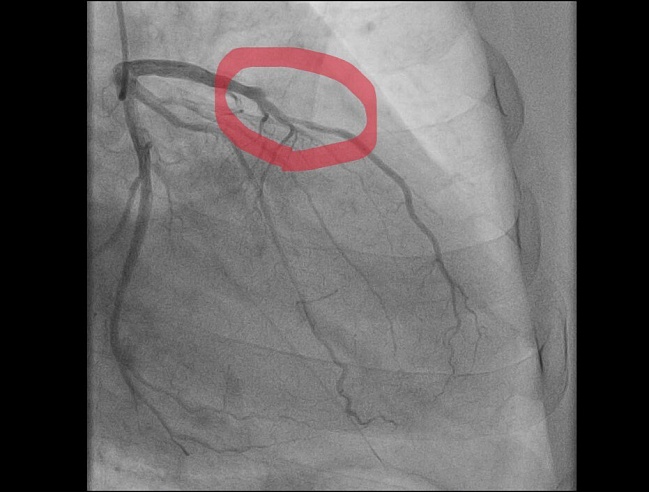

Недавний клинический случай балаковских медиков - яркий пример коварности сочетания физнагрузки и мороза: 59-летний мужчина почувствовал острую боль в груди во время уборки снега. Бригада "скорой" диагностировала "острый инфаркт миокарда" и немедленно начала лечение. Пациента доставили в сосудистый центр, где выявили тромботическую окклюзию передней межжелудочковой артерии* — сосуда, который в медицинской среде называют "артерией вдов" из-за высокого риска летального исхода при ее поражении. Операционная бригада балаковских медиков провела экстренное стентирование, полностью восстановив проходимость артерии.

"Этот случай наглядно демонстрирует необходимость дозированной физической нагрузки, особенно при сложных погодных условиях и сильном морозе. Перегрузка в сочетании с холодовым спазмом может привести к катастрофическим последствиям", — подчеркнул заведующий отделением рентгенохирургических методов диагностики и лечения БГКБ Алексей Струбалин.